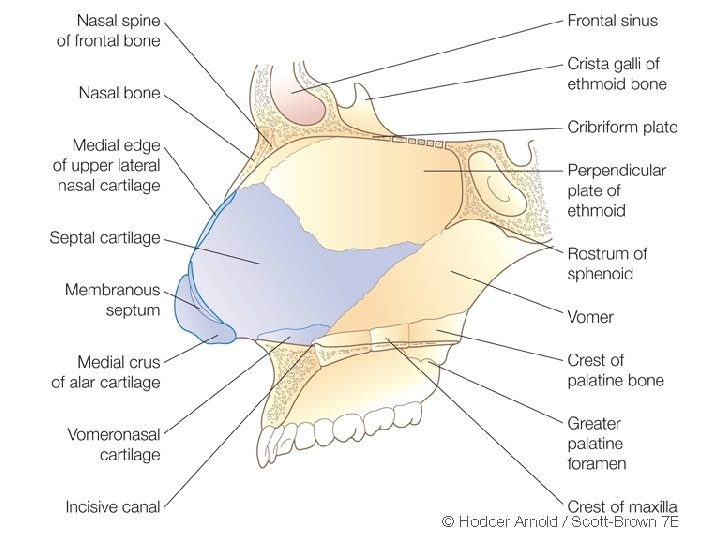

• Nasal septum consists of three parts • a) Columellar septum • b) Membranous septum (lies between columella and caudal border of septal cartilage) • c) Septum proper: consists of osteocartilagenous framework covered with nasal mucous membrane